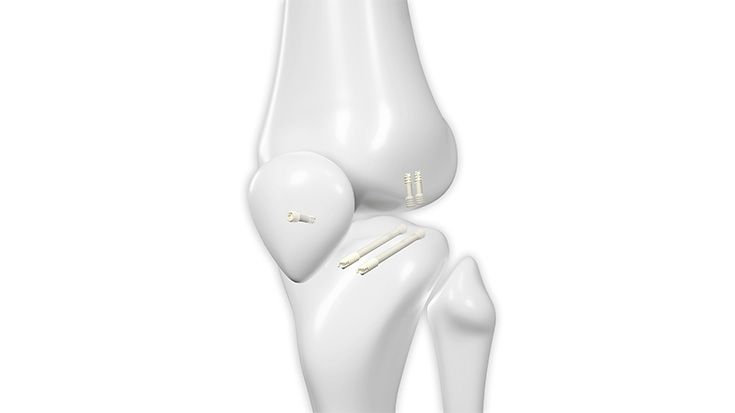

Implantate | Fuß

HBS 2 Resorb Mg und mm.CS

Nach über 100.000 erfolgreichen HBS- und HBS 2-Implantationen weltweit startet eine neue Ära mit der Erweiterung des Angebots um HBS 2 Resorb Mg Kompressionsschrauben. Diese innovative Schraube aus einer speziellen Magnesiumlegierung behält die bewährte HBS 2-Geometrie bei und ist nun zudem bioabsorbierbar. Auf diese Weise bleibt dem Patienten eine zweite Operation zur Metallentfernung erspart.

Magnesiumimplantate durchlaufen im Körper einen kontrollierten Abbauprozess, bei dem das Implantat in Knochen umgewandelt wird und Wasserstoffgas freigesetzt wird. Eine spezielle Oberflächenumwandlung verlangsamt die Korrosion des Implantats, wodurch die Abbaurate vermindert wird, was entscheidend für die Frakturheilung und die Integration des Implantats in das Knochengewebe ist.

Unser resorbierbares Schraubenportfolio, bestehend aus HBS 2 Resorb und mm.CS Implantaten unseres Kooperationspartners medical magnesium enthält kanülierte, kopflose Kompressionsschrauben in fünf verschiedenen Durchmessern. Dies ermöglicht den Einsatz in einem weiten Indikationsspektrum. Alle Schrauben sind selbstschneidend und können mit den bekannten und bewährten Operationstechniken eingesetzt werden. Lediglich das Kopfraumfräsen wird als zusätzlicher Operationsschritt ergänzt, um das Eindrehmoment beim Implantieren zu reduzieren.